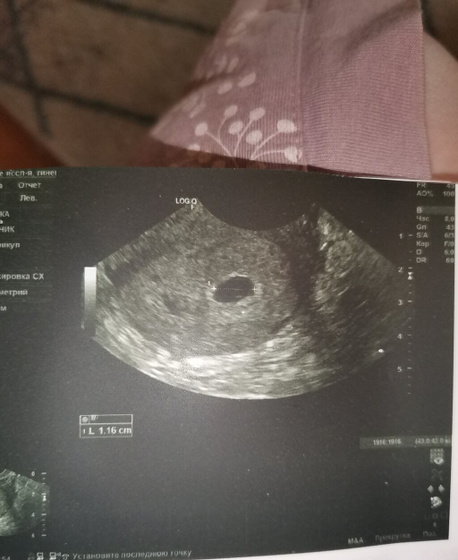

Всем приветик) Побывала вчера на УЗИ все хорошо растёт развивается?Плодное яйцо с внутренним диаметром 11мм желточный мешочек 3мм) через 10 дней можно будет послушать сердечко?главной причиной узи были ещё тянущие боли внизу живота. Слава богу отслоек нет, все ок только небольшой тонус. Сказали больше отдыхать))

Ну и фоточка с УЗИ на память